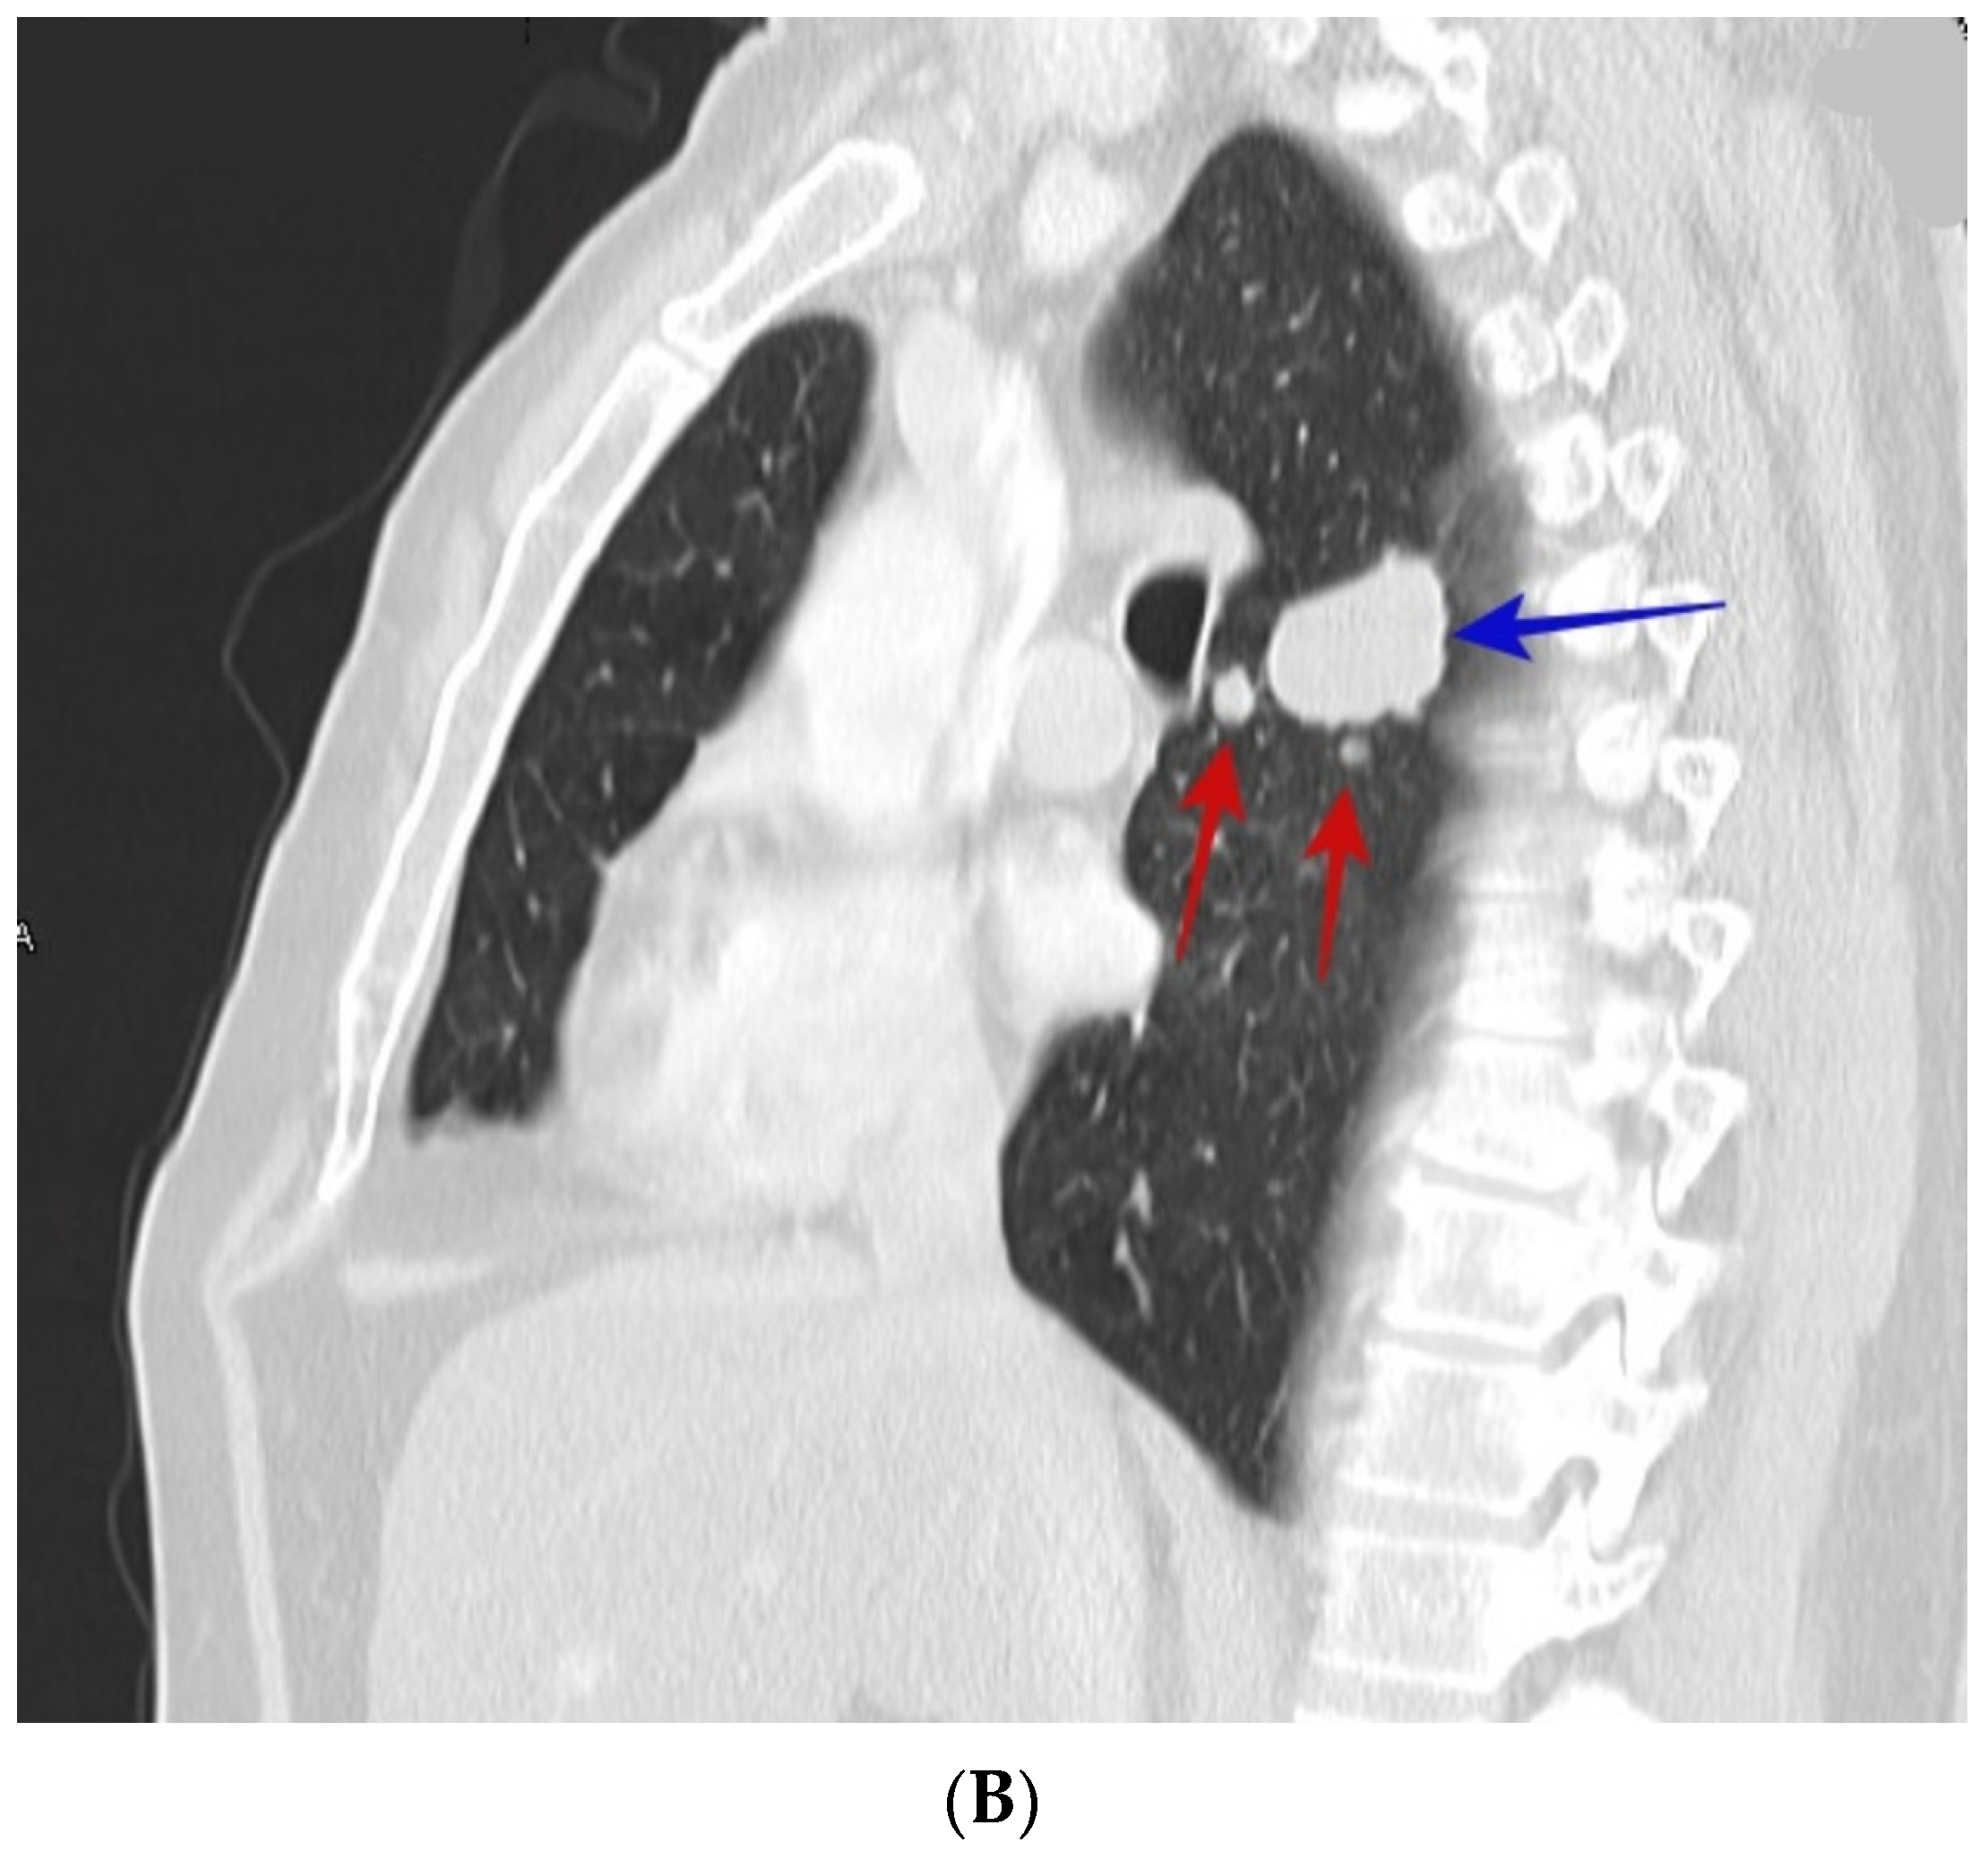

3. Results